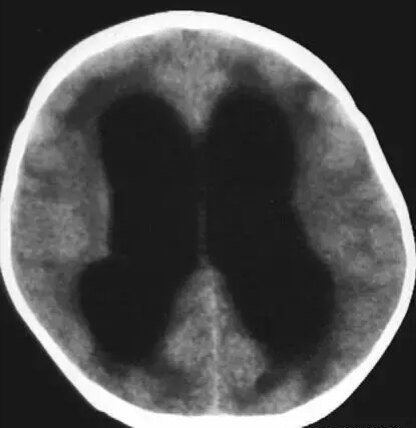

第一招:额角角度

脑萎缩~钝角

脑积水~锐角

第二招:额角比率-垂直于额角长轴测量额角的最宽部分 脑萎缩-小

脑积水~宽

第三招:脑沟和脑池脑萎缩-脑沟、脑池宽 脑梗塞——脑沟、脑池可见

脑积水——脑沟、脑池闭塞